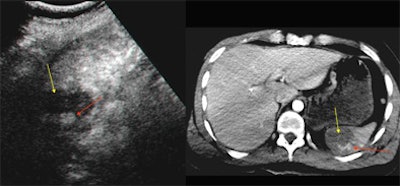

| Baseline (left) and contrast-enhanced (right) US scan of the spleen in a trauma patient. A subtle hypoechoic area is recognizable at spleen middle-third level on unenhanced image (red arrow); there is also subcapsular hematoma (yellow arrow). Contrast-enhanced image demonstrates a clear lacerocontusive perfusion defect with a central hyperechoic spot due to active extravasation (arrow). |